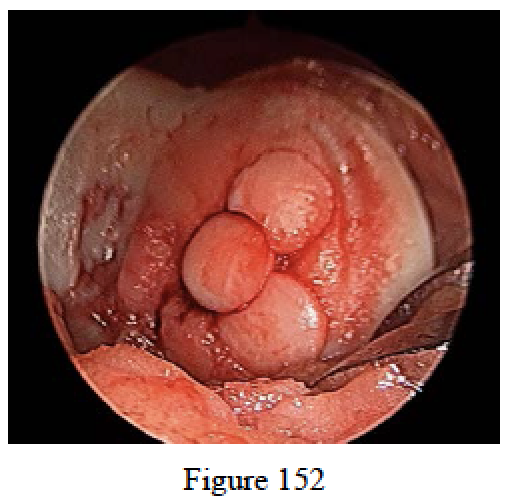

- Figure 152 is an arthroscopic view of a reconstructive procedure performed on a 28-year-old man who had a medial femoral osteochondral lesion that measured 1.5 cm x 1.5 cm. The grafts were harvested fromthe superolateral aspect of the trochlea. What is the most accurate description for the process of graftincorporation?

- The bone graft will be incorporated into the subchondral bone, and the overlying cartilageremains viable.

- The bone graft will be incorporated into the subchondral bone, but the overlying cartilage isnonviable.

- The bone graft will be incorporated while the overlying cartilage is used as a scaffold to generate a new cartilage layer.

- The bone graft will not be incorporated; healing will occur only within the cartilage layer.

- The bone graft and cartilage will both be resobred and replaced by fibrocartilaginous matrix

- The bone graft will be incorporated into the subchondral bone, and the overlying cartilageremains viable.

RECOMMENDED READINGS

O’Driscoll SW, Saris DBF. Articular cartilage repair. In: Einhorn TA, O’Keefe RJ, Buckwalter JA, eds. Orthopaedic Basic Science: Foundations of Clinical Practice. 3rd ed. Rosemont, IL: American Academyof Orthopaedic Surgeons; 2007:349-364.

Hangody L, Dobos J, Baló E, Pánics G, Hangody LR, Berkes I. Clinical experiences with autologous osteochondral mosaicplasty in an athletic population: a 17-year prospective multicenter study. Am J Sports Med. 2010 Jun;38(6):1125-33. Epub 2010 Apr 1. PubMed PMID: 20360608.